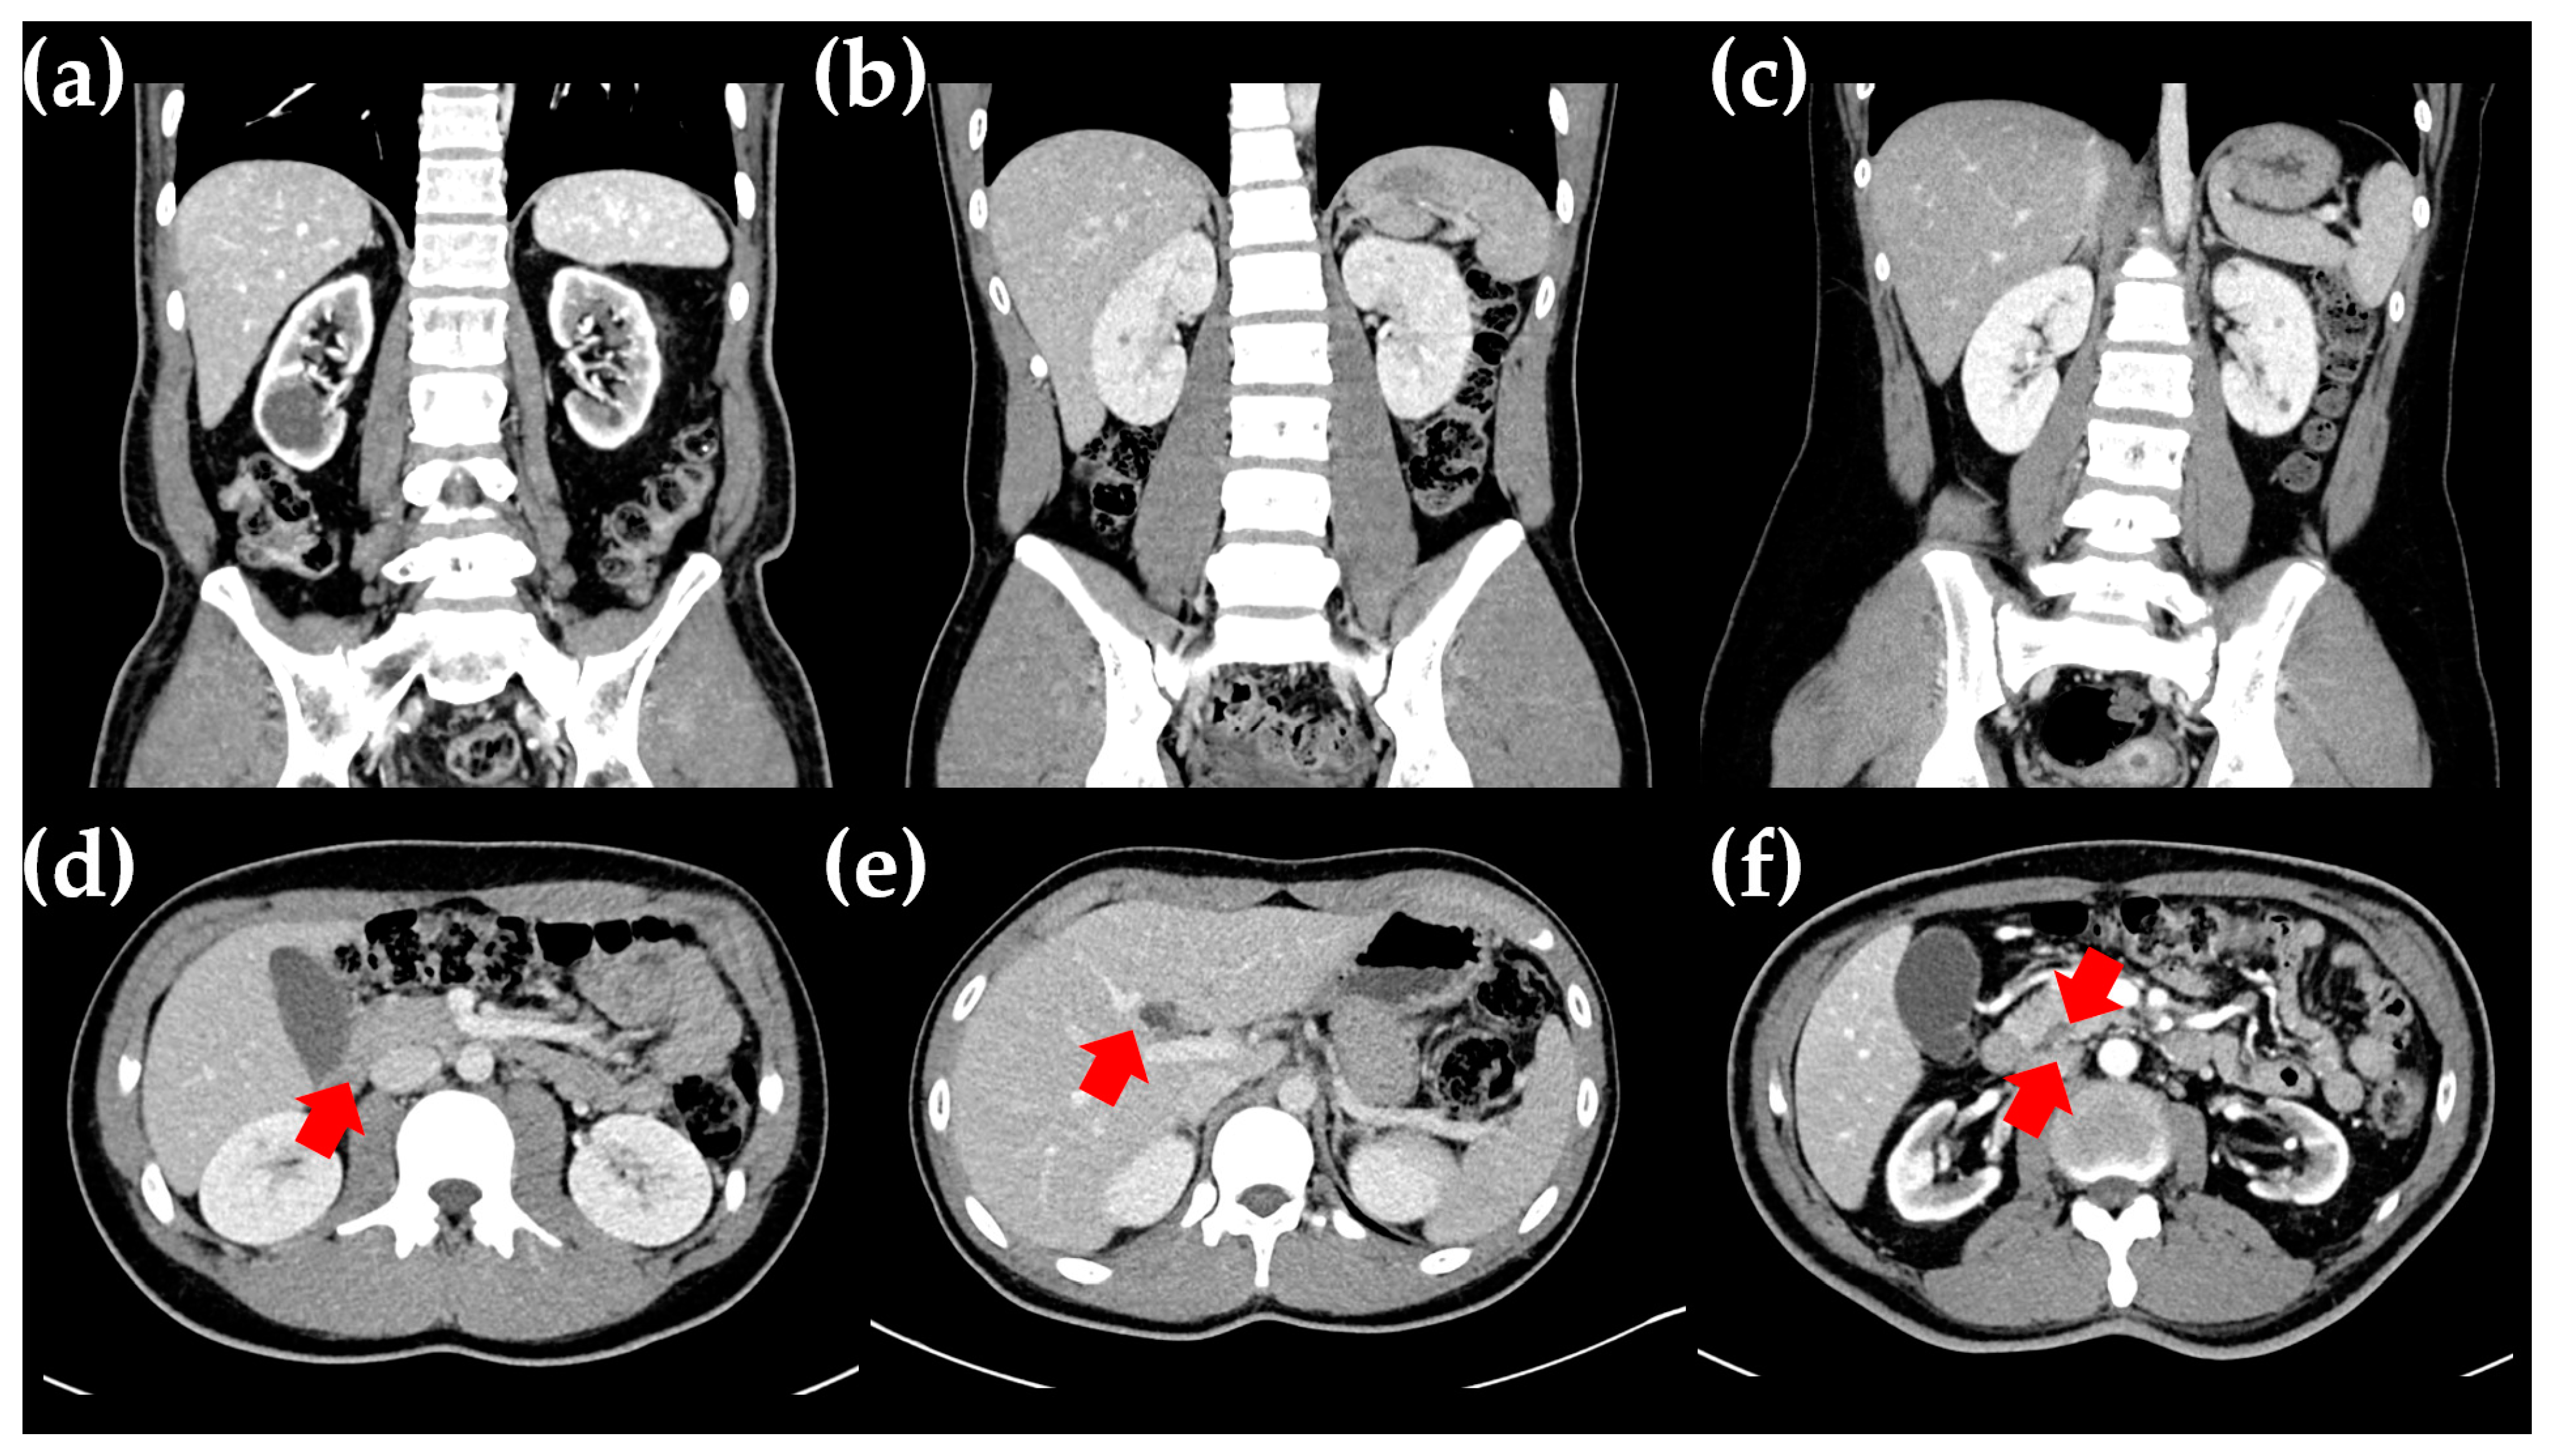

2.1. The Proband

2.2. The Proband’s Father